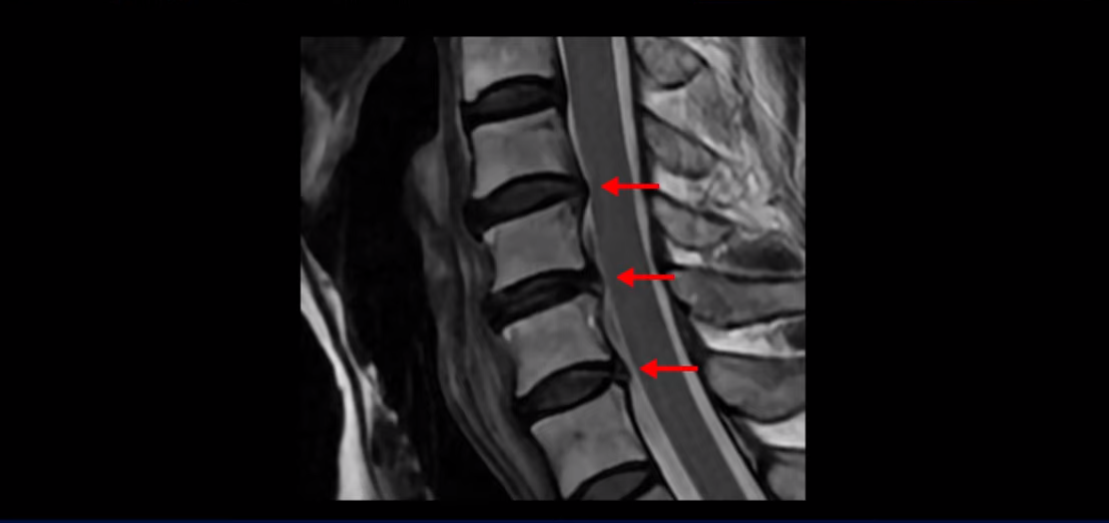

이분 MRI를 보면 세 마디의 퇴행성 목디스크가 있습니다. 4번 5번, 5번 6번과 6번 7번이 세 마디인데

디스크 파열은 4번 5번이 제일 심합니다.

중앙 오른쪽으로 수핵이 밀려 나와있고 밑으로 흘러 내려가 있습니다.

그런데 이 환자분의 방사통은 왼쪽 어깨와 팔입니다. 그래서 이 4번 5번 디스크 파열은 왼쪽 방사통의 원인이 아닌 걸로 보입니다. 6번 7번을 보면 디스크가 왼쪽으로 밀려 나와 있고, 뼈도 자라나 있습니다.

이렇게 뼈가 자라나 있으니까, 신경가지가 빠져나가는 추간공을 보면 여러 마디가 다 좁아져 있습니다.